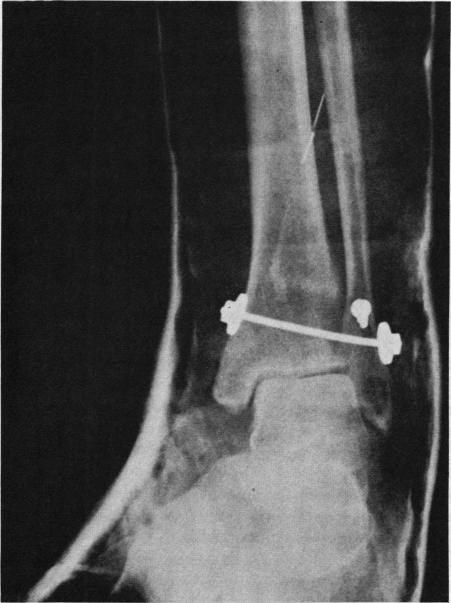

Coast Guard statistics indicate a national boating fatality rate of 9.6 deaths per 100,000 crafts. In 1977 in California, five fatalities and 70 serious injuries were directly attributable to waterskiing. The four cases reported here include three patients with propeller injuries, including one nearly fatal amputation. In each case basic measures for boating safety were overlooked.

海岸警卫队的统计数据显示,全国每10万艘船只的划船死亡率为9.6人。1977年在加利福尼亚州,有5人死亡和70人受重伤直接归因于滑水运动。这里报告的4起案例包括3名螺旋桨受伤患者,其中1人险些因截肢丧命。在每起案例中,划船安全的基本措施都被忽视了。

Orthopedic injuries in water-skiing: etiology and prevention.滑水运动中的骨科损伤:病因与预防